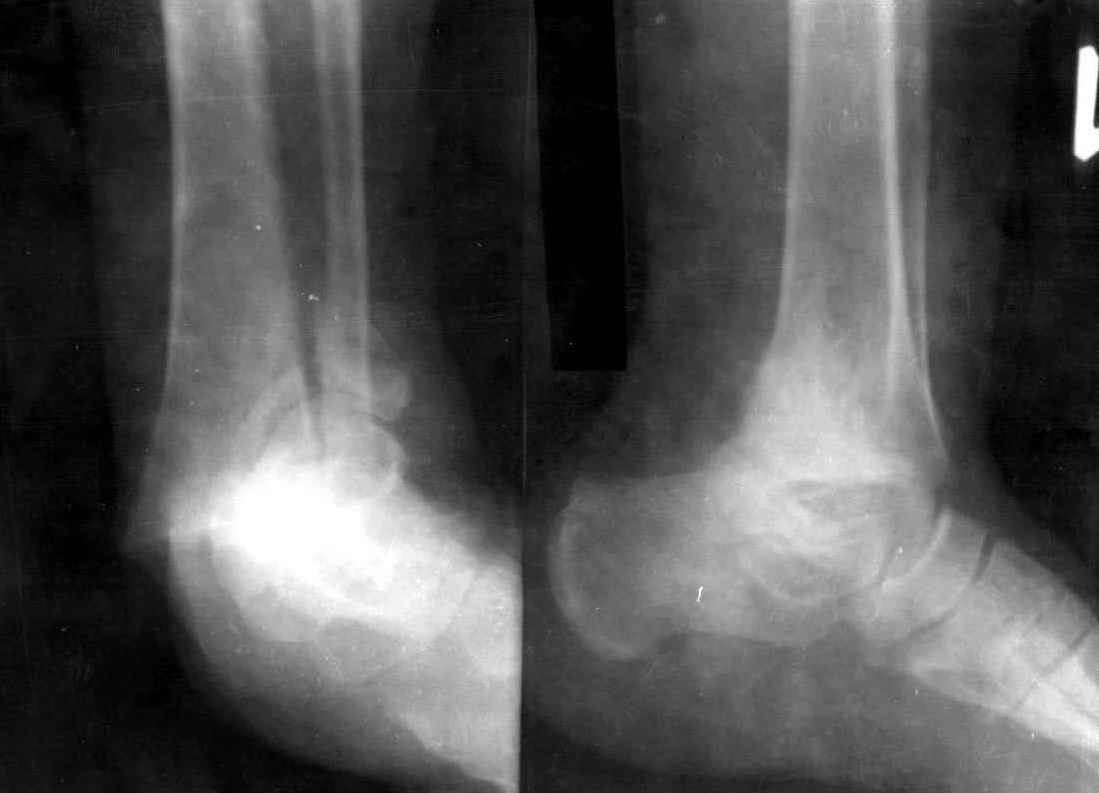

Re: Перелом обеих лодыжек и з/края б/б кости с вывихом стопы

Опарин Сергей 11 Август 2006, 23:36

Уважаемый С.А. Мелашенко!Если принимать во внимание только тип повреждения (нестабильное), то конечно показана фиксация костей, образующих голеностопный сустав, одним из способов. Но в принятии решения нельза не учитывать такие факторы как: наличие сопутствующих заболеваний, предоперационную мобильность пациентки, массу тела, выраженность остеопороза, желания пациентки (при том, что вы добились приличного стояния отломков)...